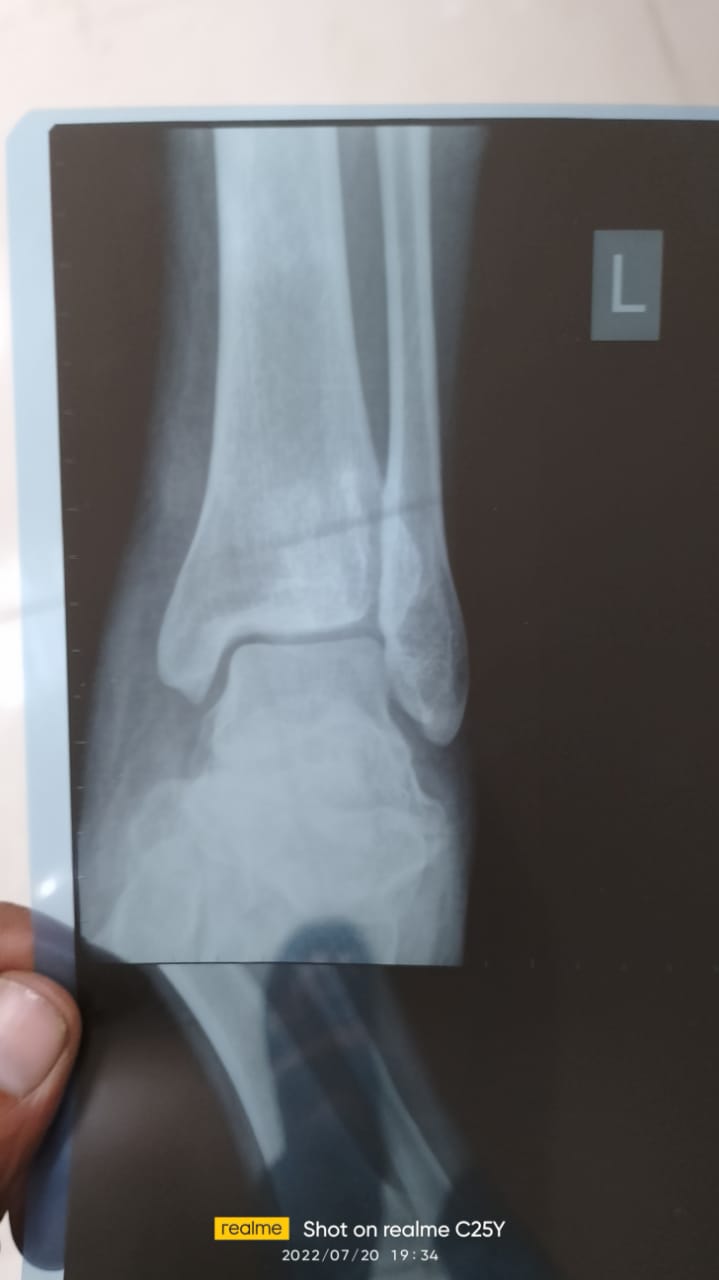

وأوضح شقيق المصاب، في تصريحات خاصة لـ القاهرة 24، أنه قد ذهب رفقة شقيقه بعدما حملته عربة الإسعاف من مدينة العاشر من رمضان وجرى تحرير المحضر اللازم بالواقعة، وتم نقل المصاب إلى مستشفى بلبيس المركزي، لتلقي الإسعافات اللازمة، وهناك تبين خطورة حالته ليتم تحويله إلى أحد المستشفيات لإجراء تدخل جراحي، قبل أن يتبين حاجته لتركيب 16 مسمارا طبيا وشريحتين جراء إصابته التي تحتاج نحو ثلاثة أشهر للعلاج.